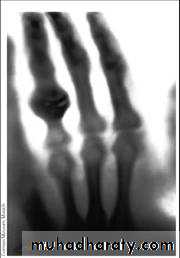

The radiograph of Bera Roentgen’s hand” taken

22 Dec. 1895• Electromagnetic spectrum :